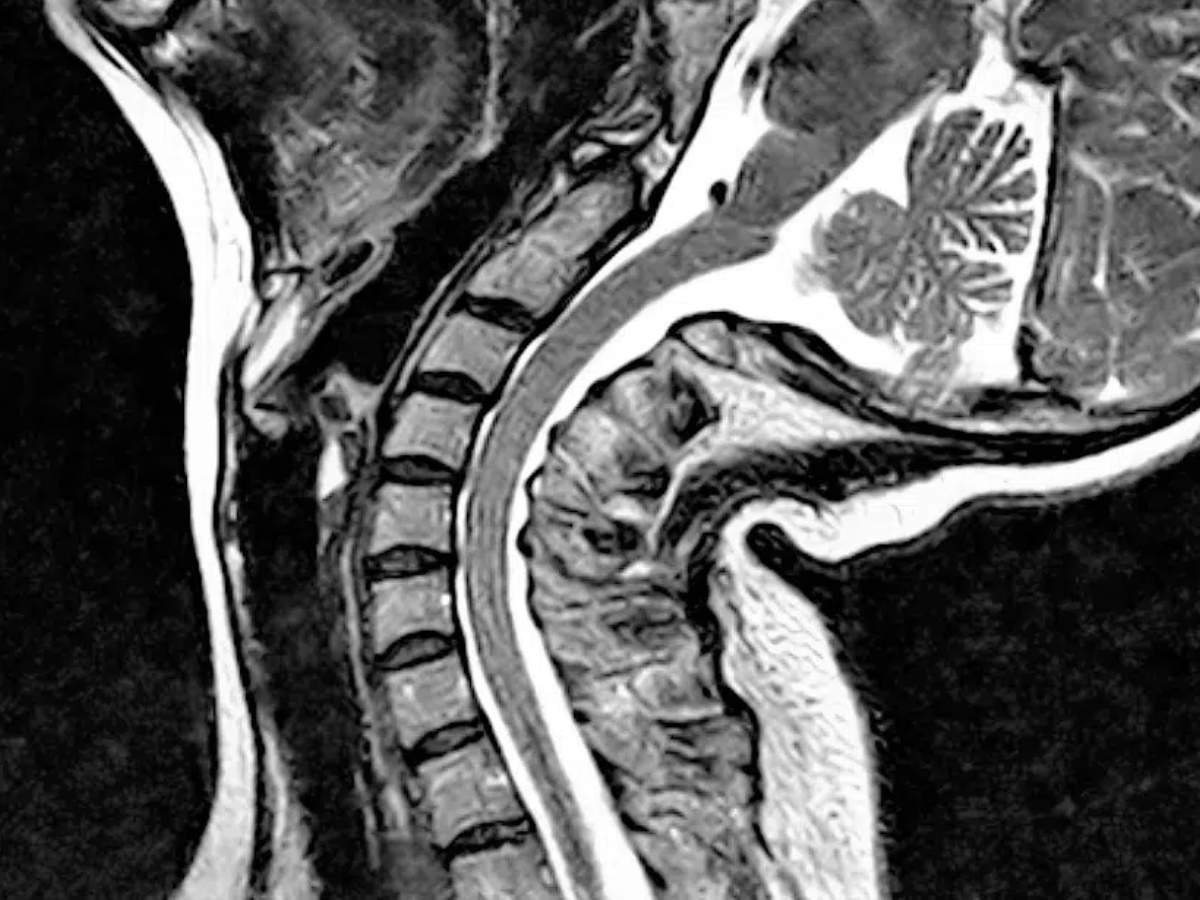

Craniocervical Instability (CCI) is a condition where the ligaments that support the junction between the skull and upper spine become weakened or damaged, causing excessive movement.

Craniocervical Instability (CCI) is a structural condition in which the ligaments and connective tissues that stabilize the junction between the skull (cranium) and the upper cervical spine (primarily the C1 and C2 vertebrae) become weakened, stretched, or damaged. This instability allows for excessive movement at the craniocervical junction, which can compress or irritate the brainstem, spinal cord, and nearby nerves.

Because these symptoms overlap with other conditions and standard imaging may miss the instability, CCI is notoriously underdiagnosed. Specialized imaging—like upright MRI or digital motion X-ray (DMX)—is often needed for accurate diagnosis.